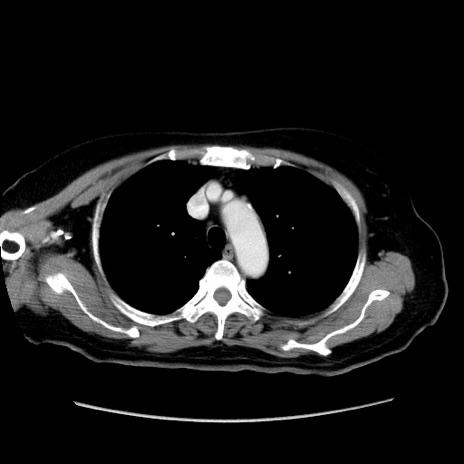

症例19(横断像)

【症例】80歳代女性

【主訴】下腹部痛

【現病歴】約8時間前より下腹部痛の出現あり、救急外来受診。

【既往歴】両側付属器切除

【身体所見】意識清明、下腹部正中に手術痕あり、その部位に一致して圧痛と反跳痛あり。腸蠕動音は亢進。

【データ】WBC 9300、CRP 0.15